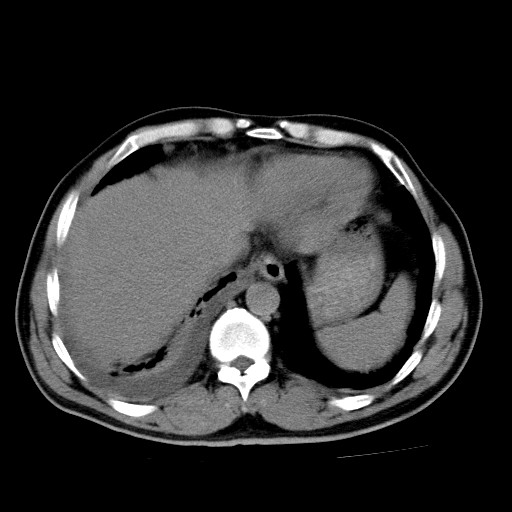

男,54岁,咳嗽,右侧胸痛10天。肺窗>150k,传不了

右肺中心型肺癌并右下肺不张,右侧胸膜纵隔转移。

右中央型肺癌并右肺下叶不张,纵隔内及右胸膜转移,右胸腔积液

考虑   右肺癌伴右下肺部分不张,阻塞性肺炎,纵隔淋巴结增大,右侧胸腔积液其他待排

考虑右肺下叶中央型肺癌并右肺下叶不张,纵隔淋巴结内及右胸膜转移。建议增强。

右下叶大片实变,肺门未见明显肿块影。有胸腔积液和纵隔内肿大淋巴结影。没有增强和肺窗,不好定。

考虑:1、右下叶周围型肺癌伴胸膜、纵隔淋巴转移?